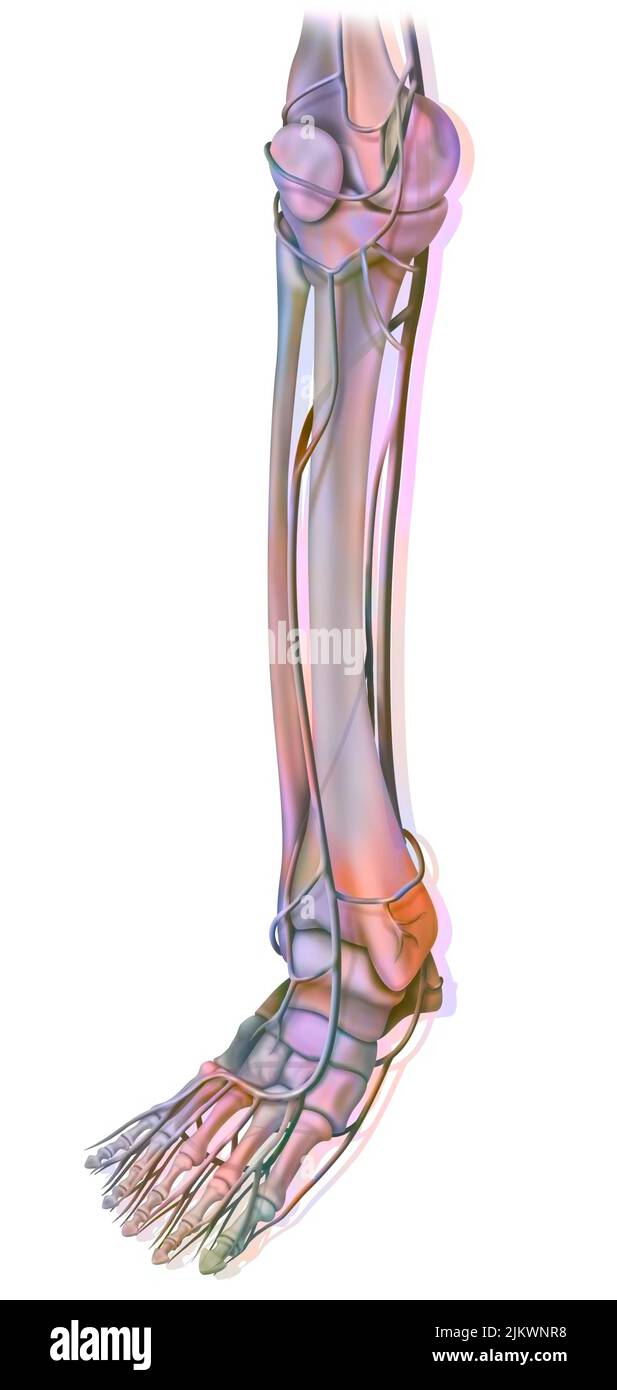

RFPR8GRD–19ème siècle illustration de la jambe gauche de l'avant après avoir enlevé la peau et le fascia. Publié dans Bilder-Atlas Conversations-Le Systematischer zum